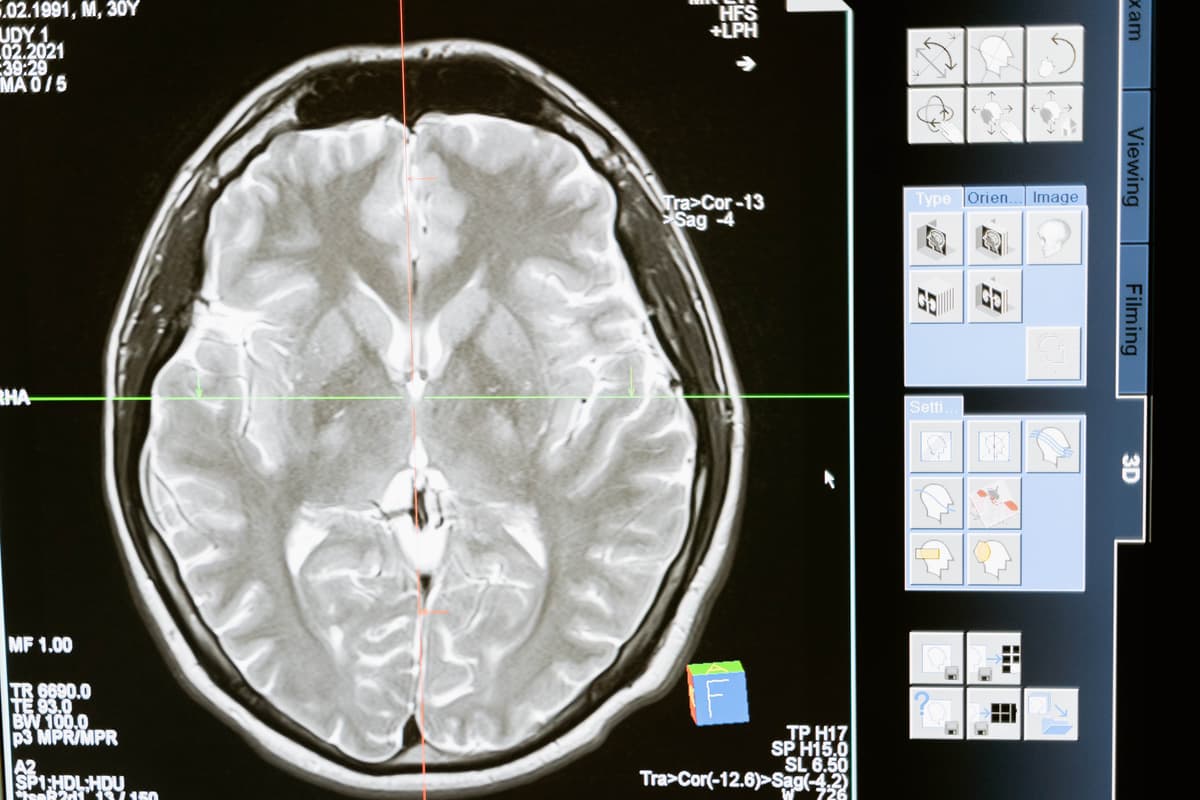

Accurate diagnosis of a brain aneurysm is crucial for determining the appropriate treatment plan. Diagnostic methods include medical imaging techniques such as magnetic resonance imaging (MRI) and computed tomography angiography (CTA), which enable healthcare professionals to visualize the blood vessels in the brain and identify any potential aneurysms.